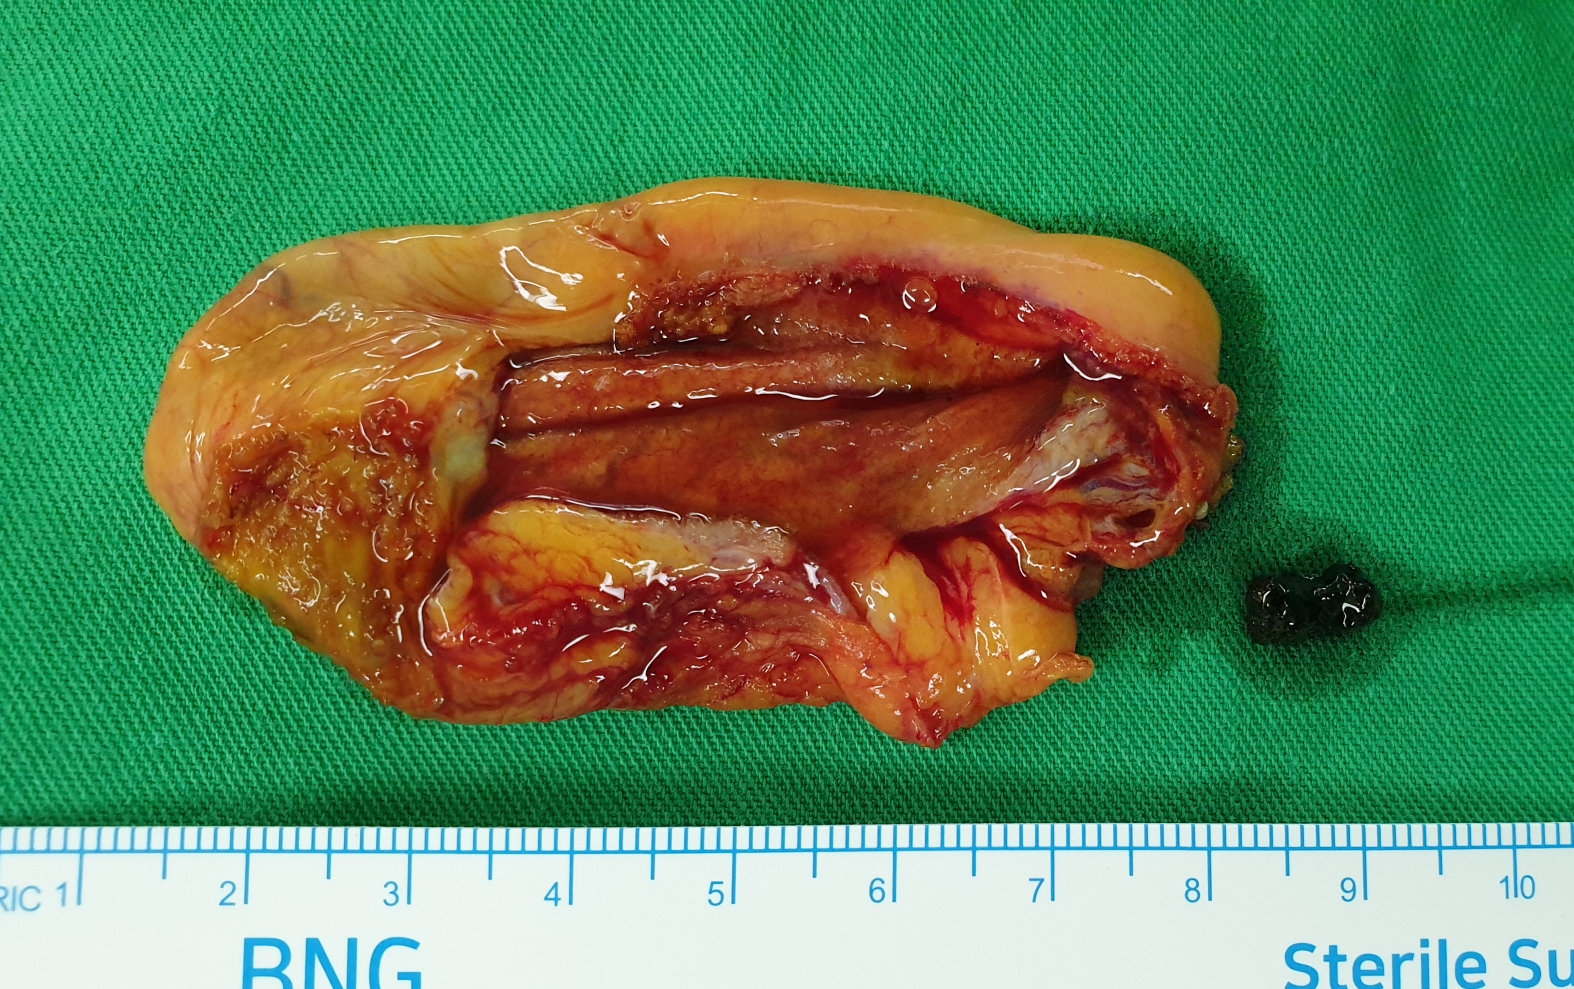

61세 남자분, 급성 담석 담낭염

평소 상복부 통증이 심했던 분입니다. 담석이 많았습니다.

30분 걸렸고 수술은 합병증 없이 잘 끝났습니다.